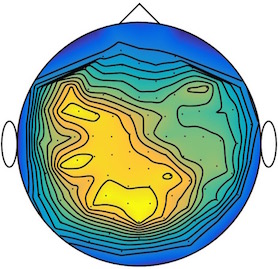

We applied our method to a magnetoencephalography (MEG) dataset. In this setup, brain activity of a subject is recorded (Elekta Neuromag, 306 sensors of which 204 planar gradiometers and 102 magnetometers, sampling frequency 1000Hz) while the subject reacted to the presentation of a target stimulus by pressing either the left or the right button.

Data is preprocessed applying signal space separation correction, interpolation of noisy sensors, and realignment of data into a subject-specific head position (MaxFilter, Elekta Neuromag). The signal was then filtered (low pass 40HZ), and artifacts such as blinks and heartbeats removed thanks to Signal-Space Projection using the Brainstorm software222http://neuroimage.usc.edu/brainstorm. The samples we used for our barycenter computations are an average of the norm of the two gradiometers for each channel from stimulation onto 50ms and the classes were left or right button.

| Class 1 | Class 2 | ||||||

|

|

|

|

|

|

|

|

| Sample 1 | Sample 2 | Sample 3 | Mean | Sample 1 | Sample 2 | Sample 3 | Mean |

|

|

|

|

|

|

|

|

This results in two classes of recordings, one for each pressed button. We aim at computing a representative activity map for each class using Wasserstein barycenters. For each class we have recordings each having samples located on the vertices of an hexahedral mesh of a hemisphere (corresponding to a MEG recording helmet). These recorded values are positive by construction, and we rescale them linearly to impose . Figure 6, top row, shows some samples from this dataset, displayed using interpolated colors as well as iso-level curves. The black dots represent the position of the electrodes on the half-sphere of the helmet, flattened on a 2-D disk.

We computed TV-regularized barycenters independently for each class by solving (16) with the TV regularization using the projected gradient descent method (22). We used a squared Euclidean metric (24) on the flattened hemisphere. Since the data is defined on an irregular graph, instead of (23), we use a graph-based discrete gradient. We denote the graph which connects neighboring electrodes. The gradient operator on the graph is

The total variation on this graph is then obtained by using , the norm, i.e. we use in (23).

Figure 6 compares the naive barycenters (i.e. the usual mean), barycenters obtained without regularization (i.e. ) and barycenters computed with an increasing regularization strength . The input histograms being very noisy, the use of regularization is important to make the area of significant activity emerge from the noise. The use of a TV regularization helps to keep a sharp transition between active and non-active regions.